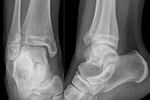

Pott's fracture[5] Percival Pott bimalleolar fracture of the ankle eversion of ankle Pott's fracture at Who Named It?